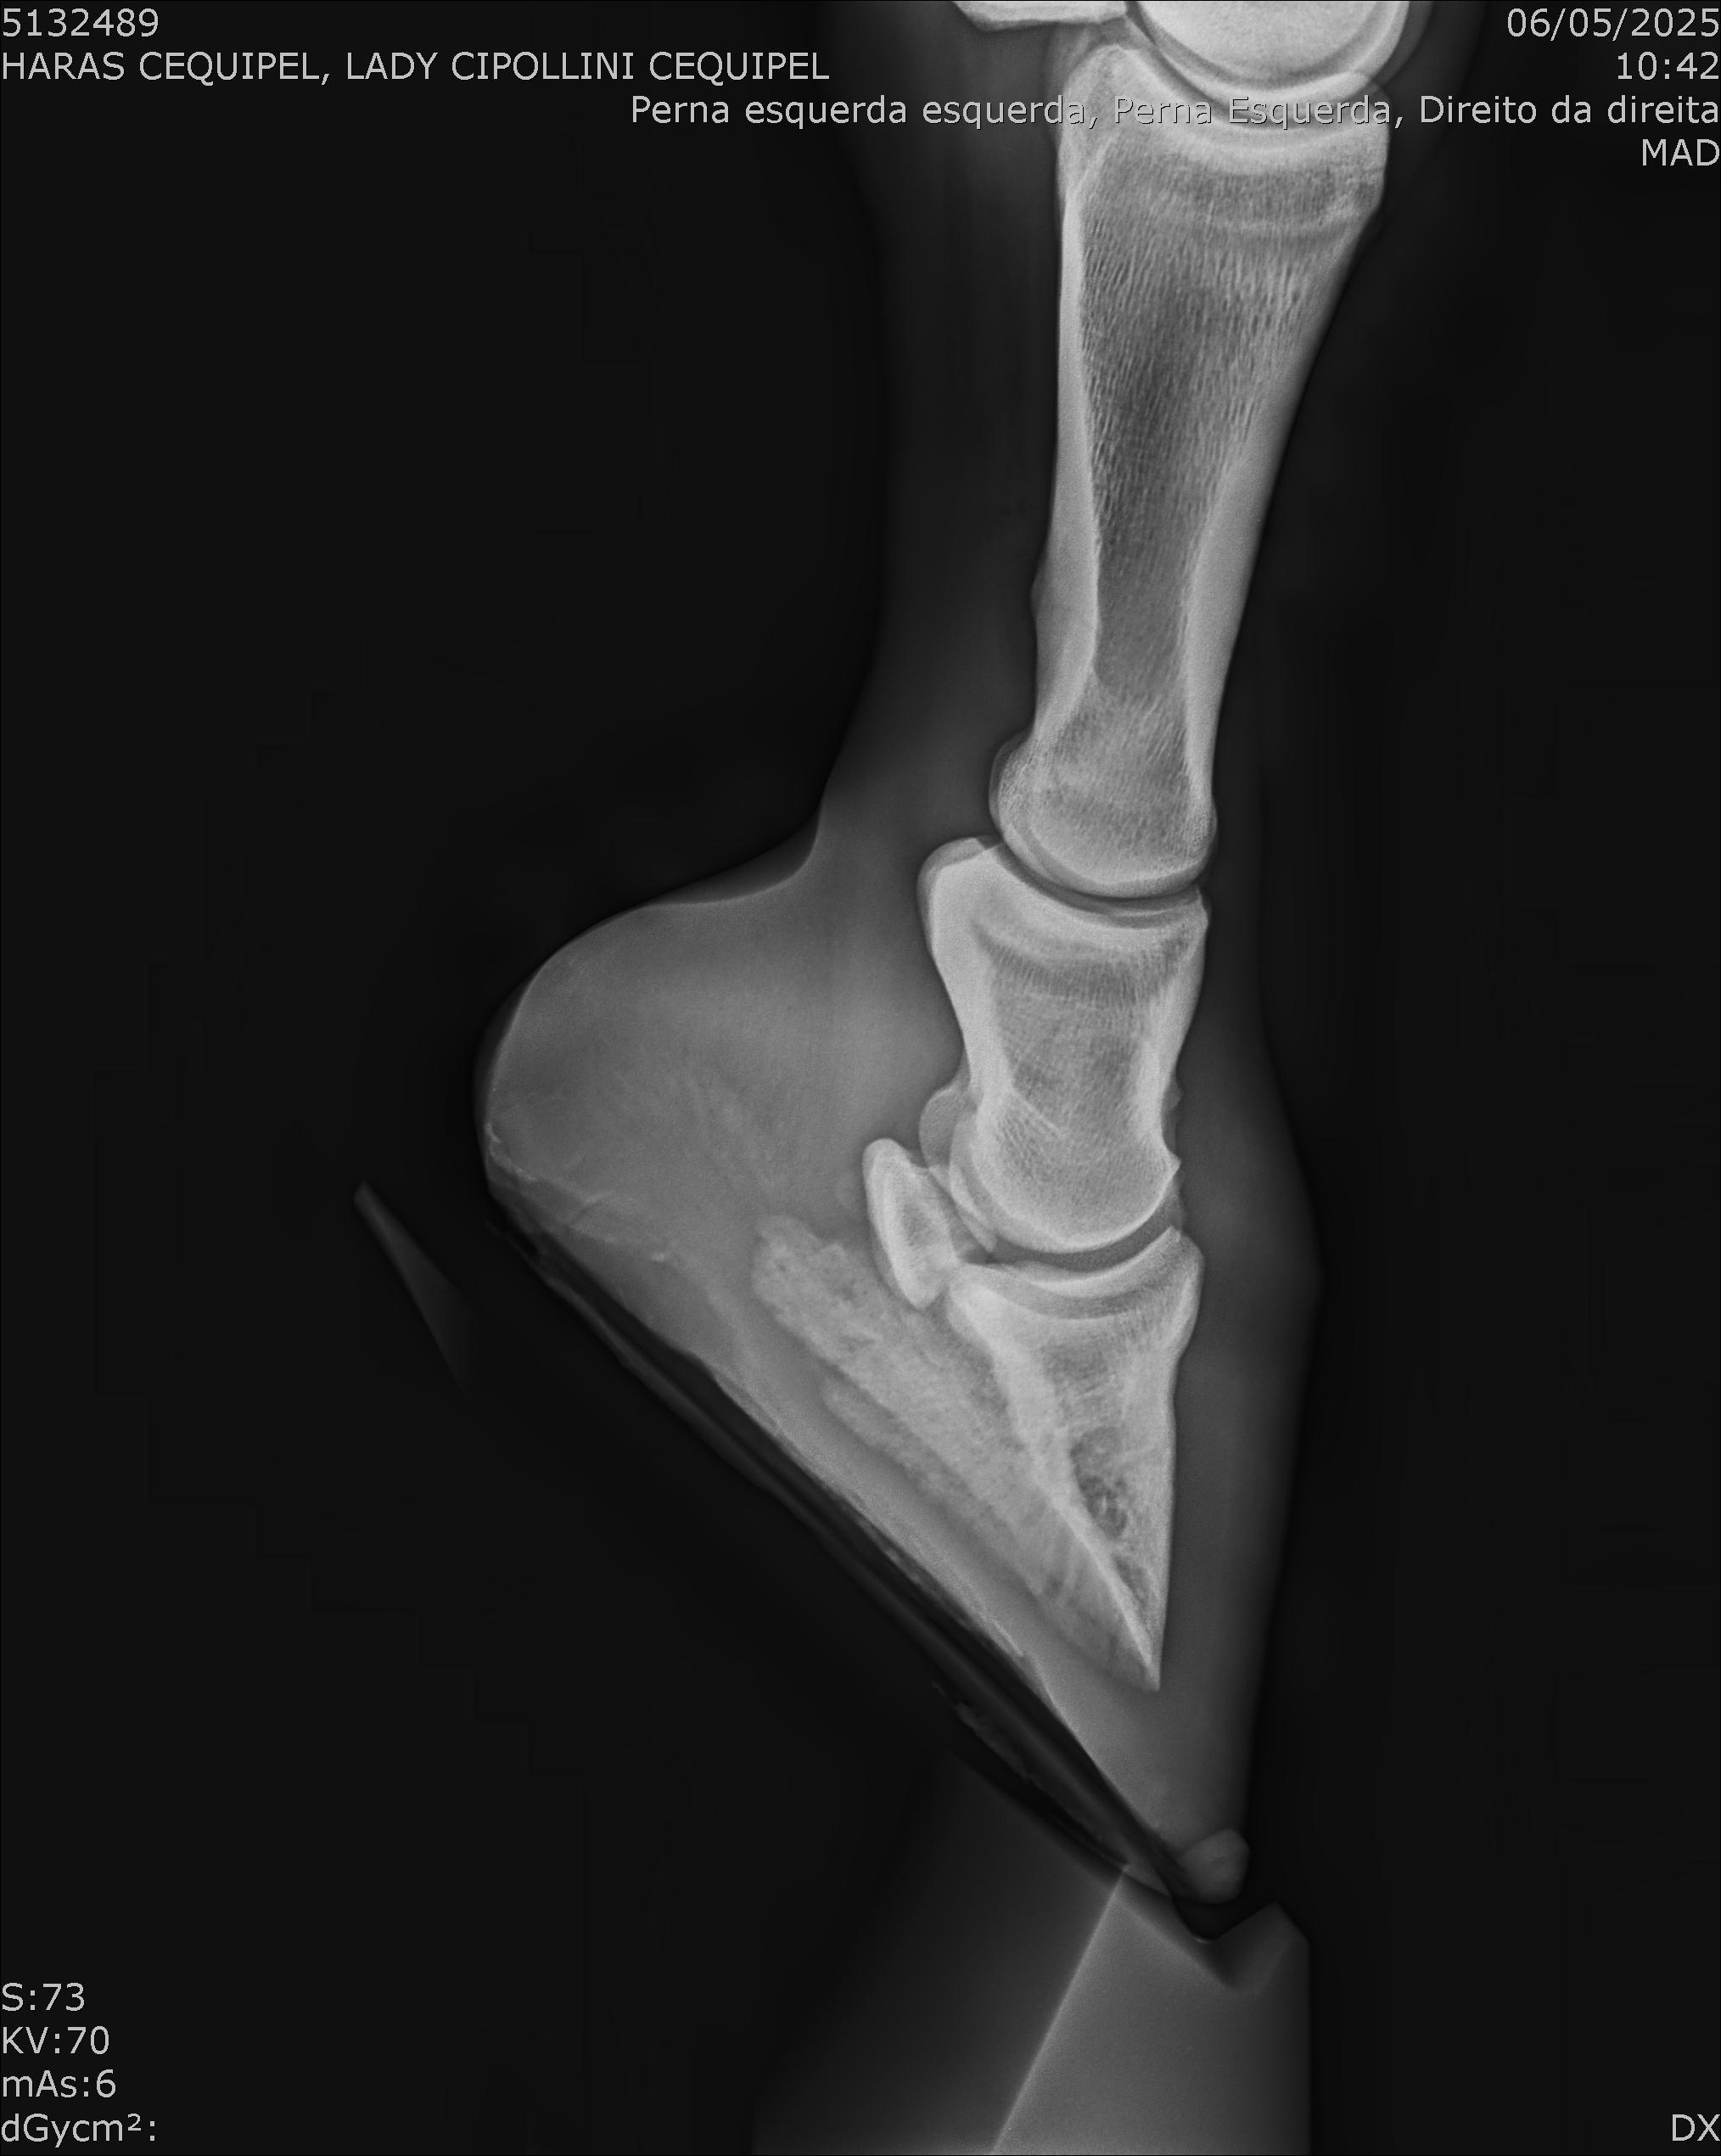

:: RAIOS-X DO LOTE